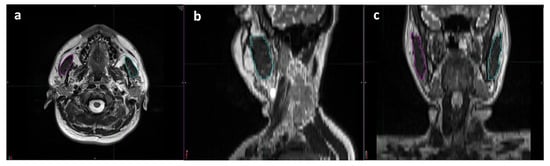

The masseter muscle, which arises from the zygomatic arch and inserts into the mandibular angle, is the largest of all the muscles involved in mastication. MRI and planning CT scans obtained for SIB-IMRT planning were co-registered for the masseter muscle delineation and TMMV (total volume of right and left masseter muscles) calculation processes. A skilled radiologist (UAP) who specializes in head and neck imaging performed all radiologic evaluations, measurements, and analyses (Figure 1). The radiologist performed volumetric analyses on the treatment planning system while maintaining a blind approach to the clinical data.

Figure 1.

Representative delineation process used for volumetric measurements of each masseter muscle using T2 weighted magnetic resonance imaging scans: (a) axial, (b) sagittal, and (c) coronal planes (magenta: right masseter muscle; cyan: left masseter muscle).